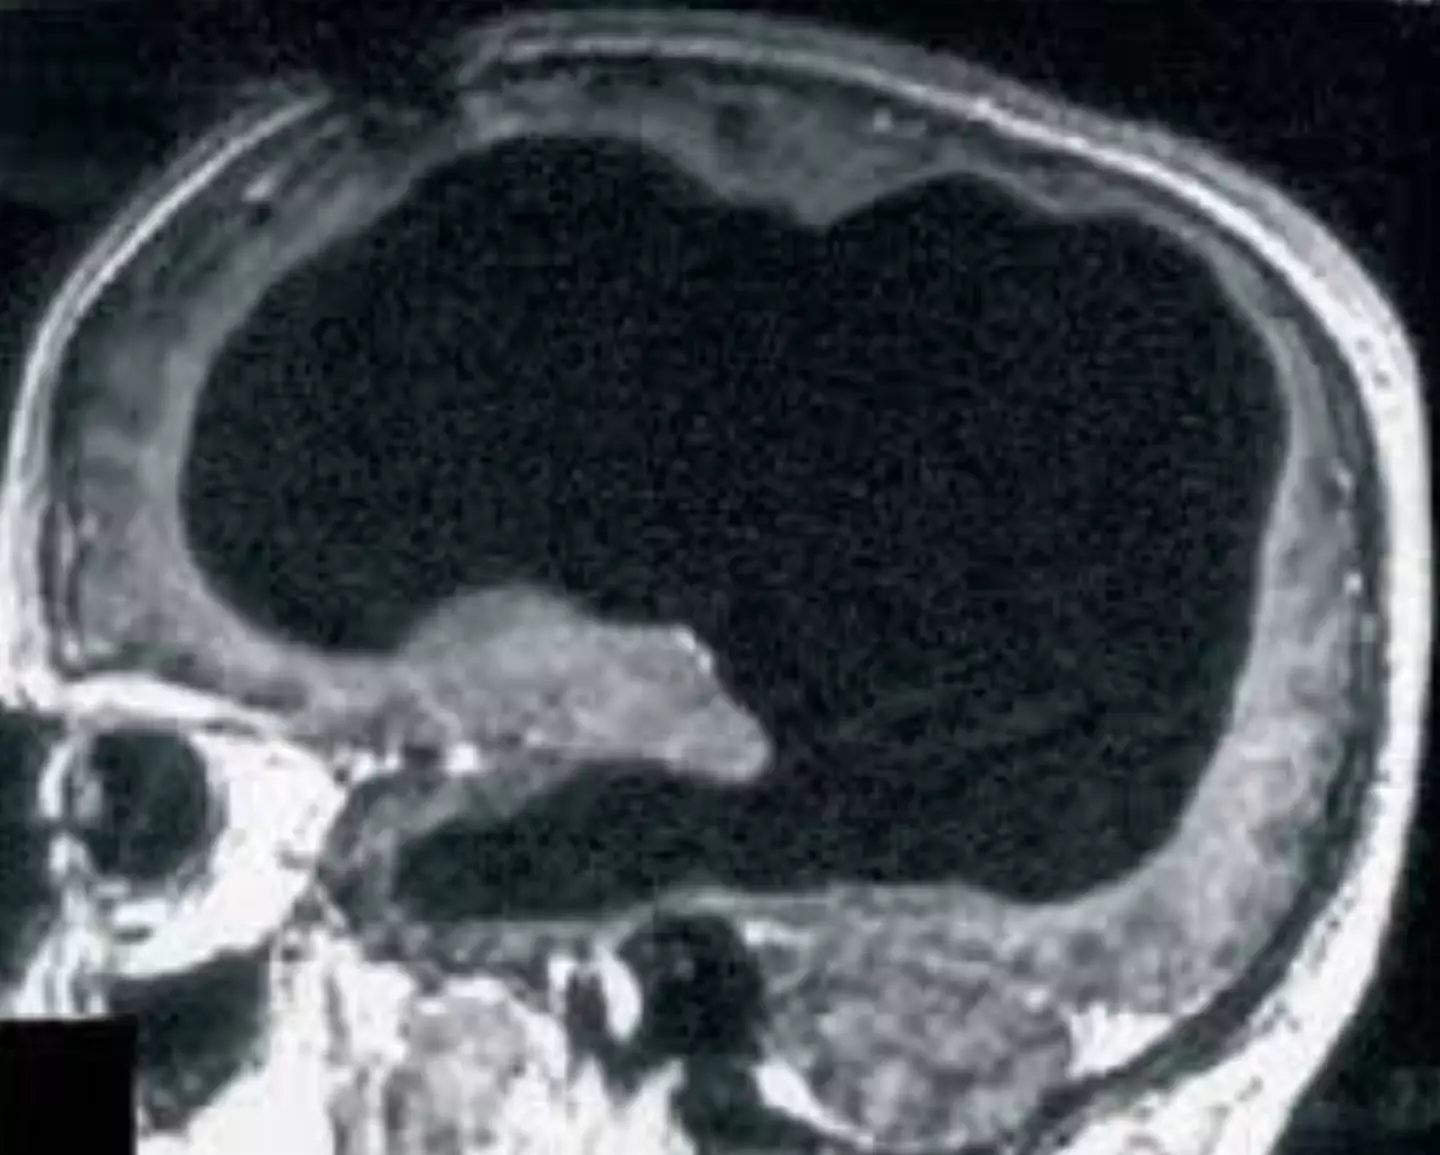

Instead, the man’s skull was essentially full of liquid with just a thin layer of brain tissue left. The condition even has a name and is known as hydrocephalus.

A scan of his brain showed just how much... well empty space there was.

Doctors believe most of his brain was slowly destroyed over 30 years by the build-up of fluid in the brain due to his condition.

Interestingly, he'd been diagnosed with it as an infant and treated with a stent, but it was removed when he was 14 years old, and since then, the majority of his brain seems to have been eroded.